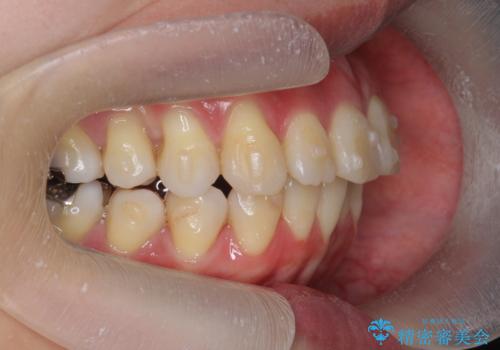

- 出っ歯に見える前歯、捻れてしまった小臼歯の改善を求めて来院されました。

マウスピースでは改善の難しい小臼歯のねじれをまず部分ワイヤー矯正で改善し、その後マウスピース矯正で前歯の突出感を改善します。

時間はかかりましたが、捻れ、かみ合わせ、前歯の角度の改善が達成され満足いただくことができました。